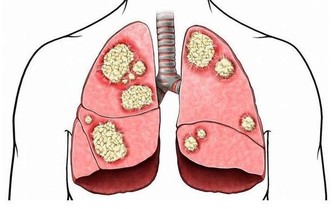

最近出了一則這樣的新聞,那就是有一位老先生,

在平時總是會感覺心窩下方有疼痛感,出現這種情況,

這位老先生只是認為是自己的胃出了毛病,吃點胃藥就可了。

可隨著時間變長,他居然摸到自己的腹部有明顯的包塊,但這並沒有引起他的注意,直到最後檢查才發現,已經是肝癌晚期了,錯過了最佳的治癒時間。

針對上文中所說的這個情況,相信大家對於平時身體出現的一些疼痛,應該有了一點警示的作用。

所以小編今天就來給大家介紹一下,在平時,我們身體出現了哪些的痛,分別暗示著什麼樣的癌症,然後對照自己的實際情況,做相應的檢查,就可以杜絕癌症的出現。